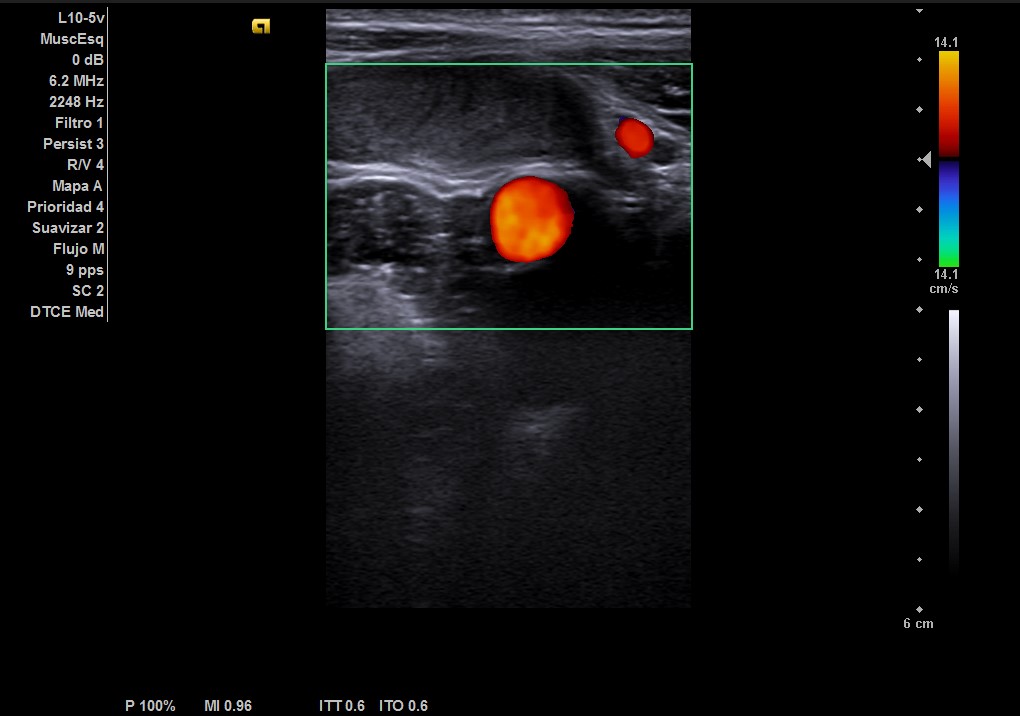

Durante la realización de la prueba, el paciente comenta que en ocasiones no encuentra el testículo derecho. Por lo que decidimos cambiar a la sonda lineal y explorar planos más superficiales donde observamos el testículo derecho, por encima del ligamento inguinal, en fosa ilíaca derecha con ecoestructura normal, homogénea y vascularización normal.